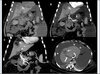

Esteatose hepática difusa associada à quimioterapia em paciente com metástases hepáticas de câncer colorretal.

A quimioterapia é um fator de indução da DHGNA.

Infiltração tumoral no lobo esquerdo simulando fígado com esteatose assimétrica.

Esteatose simulando lesões focais.

A lesão hipoatenuante próxima ao hilo hepático corresponde a área poupada de esteatose.

As lesões na imagem correspondem a esteatose multifocal/multinodular.

Esteatose focal típica no segmento IV.